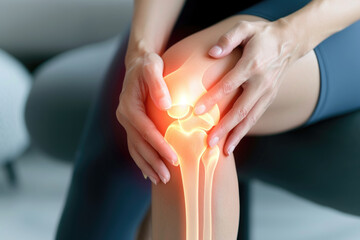

リウマチは、関節リウマチと呼ばれる自己免疫疾患であり、関節に影響を及ぼす炎症が特徴です。関節の痛み、腫れ、こわばり、そして疲労感が一般的な症状で、特に朝に強く現れることがあります。リウマチ患者の症状は、通常対称的に現れ、少しずつ悪化する傾向が見られます。これらの症状を感じた場合は、早期の診断と治療が重要です。

各種検査と症状・身体所見の確認

リウマチの診断は、まず各種検査と症状や身体所見の確認から始まります。医師は患者の関節の可動域、腫れ、こわばり、そして特に手や足の小関節に注意を払います。リウマチでは、多くの場合、滑膜の腫れとこわばりが見られ、朝起きたときに痛みやこわばりが顕著に現れることがあります。診察では超音波検査(エコー)やレントゲンなどの画像検査を行い、関節の状態やびらんなどの病変を確認します。さらに、症状が対称的に現れることも診断の重要なポイントです。他の疾患との区別も含め、これらの情報を基に医師が評価を行います。

リウマチは、早期に診断されないと、関節や組織に深刻な損傷を引き起こす可能性が高まります。特に関節リウマチでは、軟骨や骨の破壊が進行すると、関節機能が失われるため、早期の受診と適切な治療が大切です。関節リウマチの診断基準に基づく検査や、医師の指示によるチェックリストを用いた自己チェックを行うことが重要です。これにより、体質的なリウマチのリスクが確認され、早期発見につながります。

リウマチは初期症状が軽度であることもあり、症状を見逃してしまうことがあります。しかし、早期に医療機関を受診することで、病気の進行を抑え、内科的治療で関節の機能を維持することが可能です。特に、朝の関節のこわばりや腫れ、疲労感などの症状が現れた場合は、早めに専門の医療機関を訪れることが大切です。時間が経過すると関節の破壊が進行する可能性が高くなるため、早期の受診と治療が必要です。